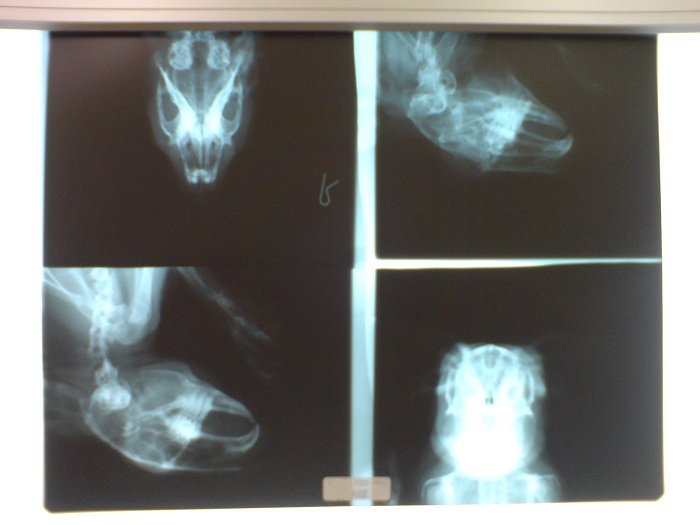

ホネホネ白茶

白茶くんのホネホネ1・2・3!

膿瘍の原因を調べるためにレントゲン撮りました(・∀・)

(画像をクリックすると大きくなります)

白茶くんはホネで見ても白茶くん だわ 。

特に左上。

/(´(エ)`)\んぶーってかんじ。

膿瘍は歯が原因していることが多いそうですが、白くんの歯はきれいでした。

歯根もきれい。

まっすぐ生えています。

いまのところ膿瘍のはっきりした原因わからず。

さて、で、上のレントゲン写真をみても、何がなにやらわからないと思うので、毛有りバージョンがこちら。